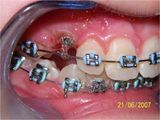

- Chirurgia mucogengivale

- Gengivectomia-gengivoplastica

- Frenulectomia

- Allungamento di corona

- Parodontologia

- Mucositi-perimplantiti